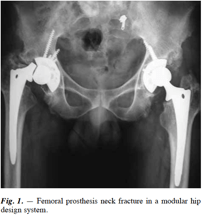

Femoral Prothesis Neck Fracture

Fracture of the femoral prosthesis neck following total hip arthroplasty is not common. We report a case of femoral prosthesis neck fracture in an adult male patient following modular, uncemented total hip arthroplasty.

This case report further emphasizes the importance of the potentially high loading situation in the prosthetic femoral neck.

On the other hand, the occurrence of a femoral prosthesis neck fracture in a cementless system denotes a well fixed distal stem and calls for a difficult revision procedure usually requiring an extended trochanteric osteotomy forstem retrieval.